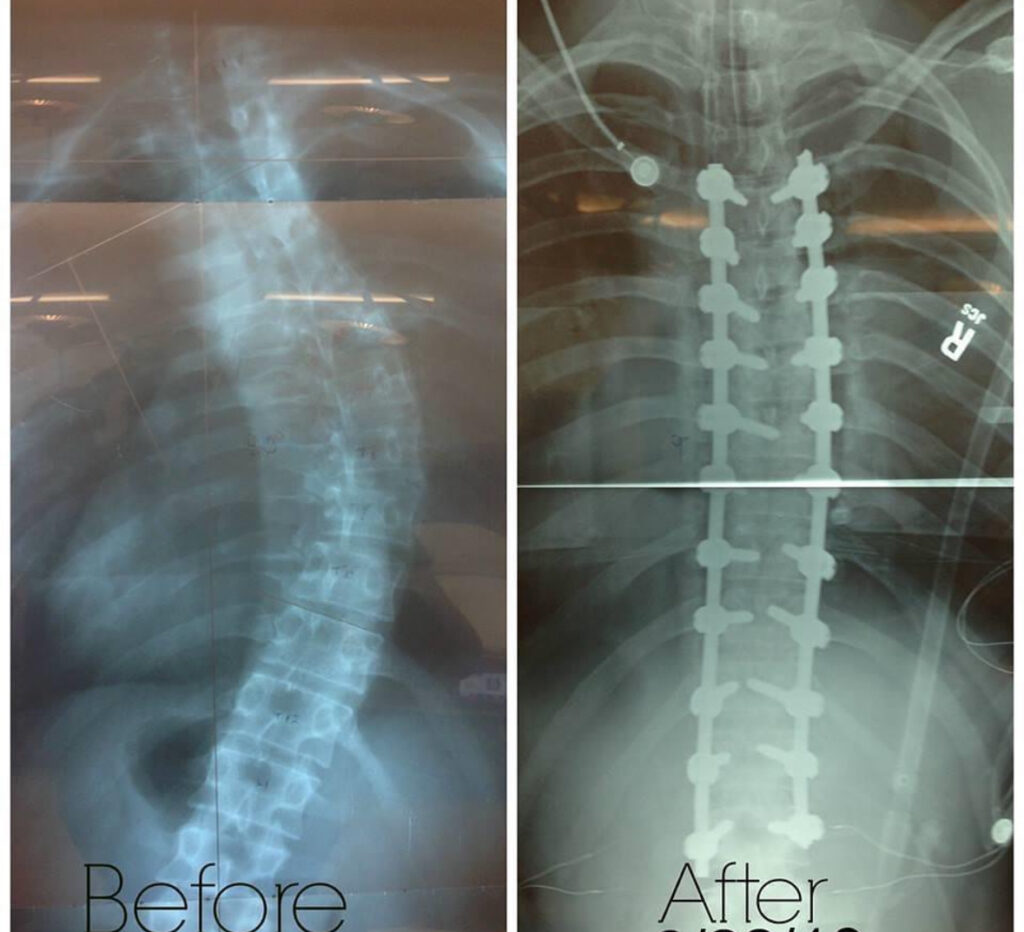

By the time I was 23, I could physically feel that my spine was getting worse. The pain became constant – not just physically, but emotionally as well. It took a toll on my energy, my confidence, and my day-to-day life. I finally saw a specialist who confirmed what I had suspected: I had a 47-degree thoracolumbar curve – meaning my spine curved through both the thoracic and lumbar regions. He said I qualified for spinal fusion surgery, and I made the decision to go for it.

The surgery wasn’t easy, and recovery was even harder. I spent several days in the hospital, then returned home where the real work began. The pain during recovery was intense at times, but I kept reminding myself that it would be worth it. And I was right. A few months later, after a lot of physical therapy, I started to feel like myself again – only better. My curve is now around 9 degrees, and I am no longer in constant pain.